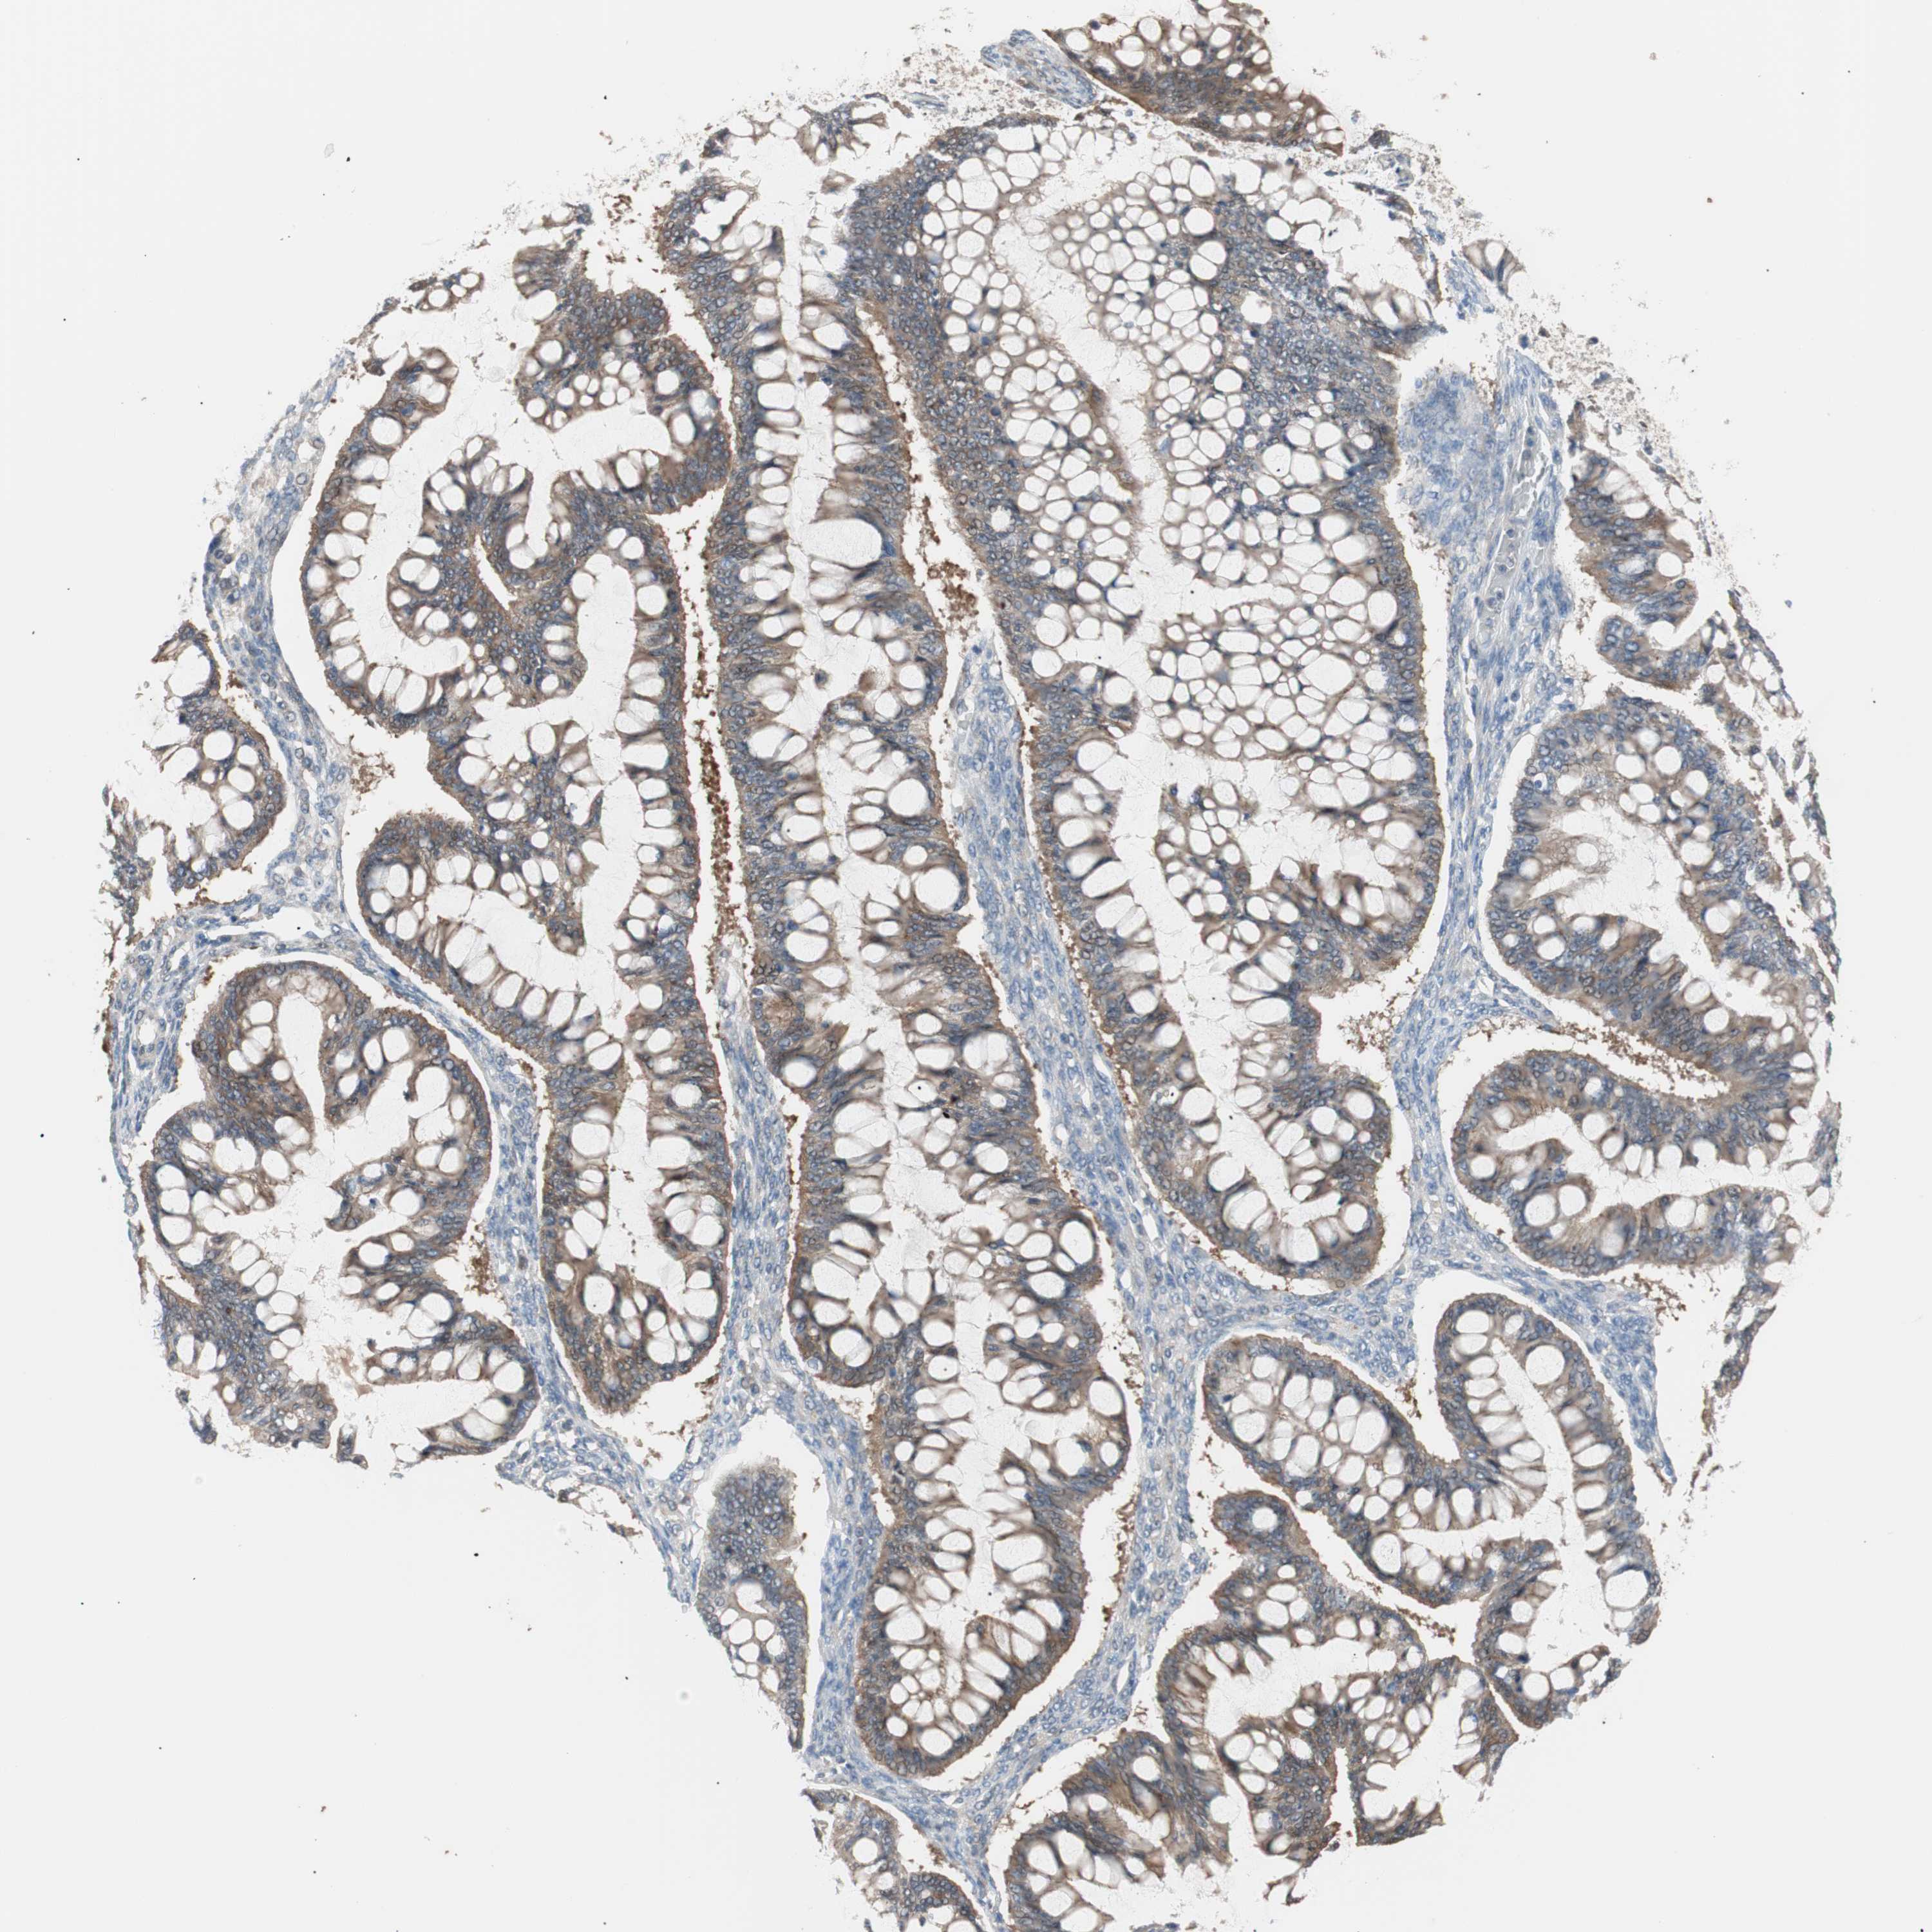

OVARIAN CANCER - Protein expressioni

A mouse-over function shows sample information and annotation data. Click on an image to view it in a full screen mode. Samples can be filtered based on level of antibody staining by selecting one or several of the following categories: high, medium, low and not detected. The assay and annotation is described here.

Note that samples used for immunohistochemistry by the Human Protein Atlas do not correspond to samples in the TCGA dataset.

Antibody stainingi

Antibody staining in the annotated cell types in the current human tissue is reported as not detected, low, medium, or high, based on conventional immunohistochemistry profiling in selected tissues. This score is based on the combination of the staining intensity and fraction of stained cells.

Each image is clickable and will lead to virtual microscopy that enables deeper exploration of all samples and also displays staining intensity scores, fraction scores and subcellular localization as well as patient and tissue information for each sample.

Antibody HPA006277

Cystadenocarcinoma, mucinous, NOS